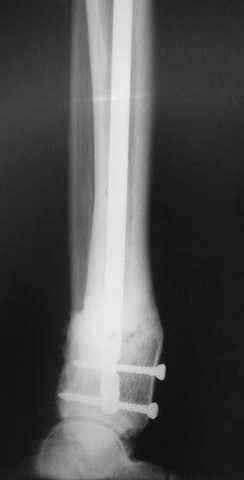

1 - рентгенограмма (прошу прощения за качество) при поступлении;

Произведено ПХО, acute shortening (5 см), фиксация стержневым аппаратом Hoffman.

3,4 - через 4 недели наложен спице-стержневой аппарат, произведена остеотомия большеберцовой кости в верхней трети, раны зажили, проводилась дистракция в аппарате.

5, 6 - через 2,5 мес после травмы выполнен закрытый остеосинтез блокируемым штифтом.

7, 8, 9, 10, 11 - через 8 мес после травмы перелом сросся.